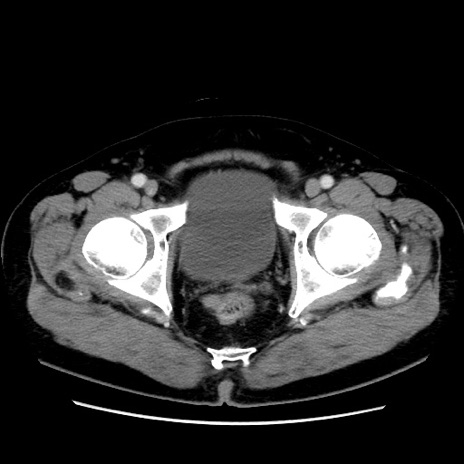

症例16(横断像)

【症例】 70歳代男性

【主訴】 腹痛、嘔吐

【現病歴】 約1ヶ月前より間欠的に腹痛と嘔吐あり、当院消化器内科を受診したところCTで多発する肝臓のLDAを指摘され、精査中であった。以降は消化器症状は安定していたが、2日前より嘔気と腹痛があり、同日より排便・排ガスが消失した。改善認めず、 本日、救急外来を受診した。

【既往歴】 大腸ポリープ切除後。

【身体所見】意識清明・会話良好、BT 36.3℃、BP 127/80mmHg、 P 80bpm、腹部:膨満あり、平坦・軟、上腹部正中および下腹部正中に圧痛あり、反跳痛なし、筋性防御なし。

【データ】WBC 7200、CRP 0.77